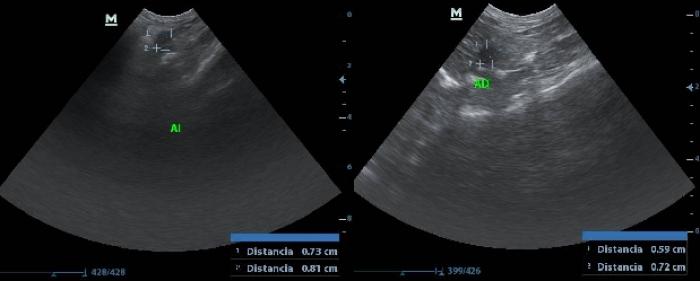

La enfermedad de Cushing o hiperadrenocorticismo se produce por la presencia de un cortisol persistentemente elevado debido a la sobresecreción de la hormona adrenocorticotrópica (ACTH) dependiente de la hipófisis o a la sobreproducción de cortisol dependiente de las glándulas suprarrenales. El hiperadrenocorticismo se ha descrito en muchas especies, incluyendo cobayas, en las cuales se considera una afección endocrina rara. El primer caso de neoplasia adrenal se describió en 1930 y desde entonces son pocos los estudios que se han realizado al respecto, pero se ve que van aumentando los casos y estudios al respecto en los últimos años14. Entre los síntomas descritos destacan la alopecia bilateral simétrica no pruriginosa, poliuria-polidipsia y otros signos más inespecíficos como atrofia muscular, exoftalmo bilateral, piel con pérdida de elasticidad y más delgada, pérdida de peso, distensión abdominal, obesidad y letargo. El diagnóstico se basa en distintas pruebas dependiendo del tipo de muestra. En el caso de muestras de orina se puede realizar el ratio cortisol/creatinina. A pesar de considerarse la prueba menos fiable, es la menos invasiva. Puede realizarse con muestras de orina recogidas en casa mediante micción espontánea para que los resultados no se vean tan afectados por el estrés del paciente. También pueden utilizarse muestras de sangre, realizándose en este caso la medición de cortisol basal, post-estimulación por ACTH o post-depresión con dexamentasona. Esta muestra es la más extendida en otras especies como el perro y el gato, siendo más fiables, pero en cobayas puede suponer un desafío, no solo el obtener el volumen y calidad de muestra suficiente si no porque la carga de estrés puede interferir en la interpretación del resultado obtenido. Finalmente, en esta especie se ha introducido el uso de la saliva para medir el cortisol basal y post-estimulación con ACTH. Este es un método más o menos invasivo pues va a depender de si el animal requiere o no sedación para su recolección o si el tutor es capaz de tomar la muestra desde casa, pero es muy fiable y el que más se está extendiendo en medicina humana pues en la saliva, el cortisol obtenido es equivalente al cortisol libre y este está menos influenciado por interferencias que el cortisol total. Además, evita problemas debidos a la gran cantidad de cortisol basal en sangre que pueden tener las cobayas de forma normal y evita las fluctuaciones de concentración relacionadas con el estrés. Todo esto hace que esta sea la muestra de elección, aunque quizá el mayor hándicap de este método sea el valor económico7,12. Tambien en estos casos es recomendable realizar estudios ecográficos con mediciones de las glándulas y estudios del aspecto en busca de posibles neoplasias (Figura 2).

Se han realizado varios estudios desde 1940 hasta, el más reciente en 2024, en los cuales se ha estudiado el tamaño y peso de estas glándulas. En el último estudio publicado en 2014, en el que se valoraba el peso de estas glándulas en 3 cobayas hembras sanas, se obtuvieron unos resultados de 0.35 ± 0.05 g para la derecha y 0.4 ± 0.05 g para la izquierda3. En cuanto al tamaño, el último estudio realizado en 2024, aporta mediciones mediante el estudio ecográfico en 20 cobayas sanas, dando como resultado para la glándula suprarrenal derecha un largo medio de 11.55 ± 1.52 mm, un ancho medio del polo craneal de 4.69 ± 1.34 mm y para el polo caudal de 4.04 ± 0.75 mm; y en el caso de la glándula suprarrenal izquierda un largo medio de 12.64 ± 2.11 mm, un ancho medio del polo craneal de 4.83 ± 1.03 mm y para el polo caudal de 4.8 ± 1.23 mm4. Teniendo en cuenta estos parámetros y que el peso de las cobayas oscila entre 500 y 1500 g, si se compara con el perro (en el cual se han reportado dimensiones normales de entre 10 y 50 mm de longitud y 2 y 12 mm de grosor), o con gatos de menos de 4 kg (en los cuales se ha visto una longitud de 7.3 ± 2.1 mm y un ancho de 3.1 ± 0.6 mm para la adrenal izquierda; y una longitud de 7.7 ± 1.7 mm y un ancho de 3.2 ± 0.4 mm), se observa que el tamaño de las adrenales en cobayas es proporcionalmente más grande que en perros y gatos. Esto quizá podría explicar porque esta especie es probablemente de las más estresables de las que acuden a consulta de los denominados nuevos animales de compañía5,6. Las glándulas adrenales de cobayas tiene una baja eficacia, pero compensan muy bien gracias a su gran tamaño, llegando incluso a presentar concentraciones basales de cortisol basal varias veces superiores a las observadas en el gato y en el perro, lo cual también se asocia a la mayor frecuencia de liberación pulsátil de ACTH11,12.